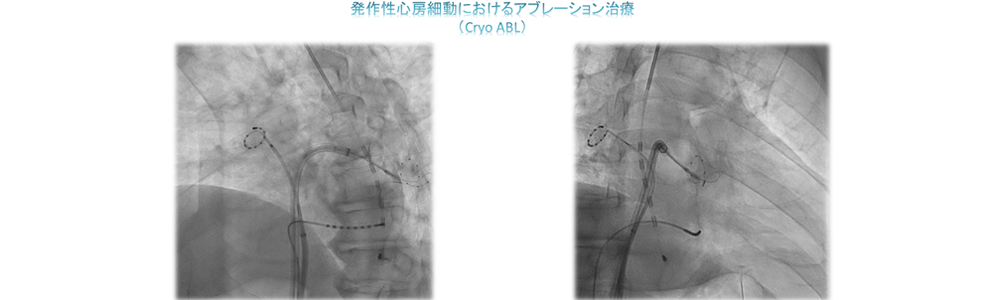

一方治療には、狭くなった冠動脈にステントを留置する冠動脈ステント留置術(PCI)をはじめ、心臓以外の動脈や静脈を拡張させる血管拡張術(PTA)、頻脈性不整脈の原因となる電気回路を遮断させるため、心筋に高周波電流を流して焼灼するアブレーションや、徐脈性不整脈に対するペースメーカー埋込術(PMI)、除細動器のデバイス埋め込み術(ICD)などがあります。